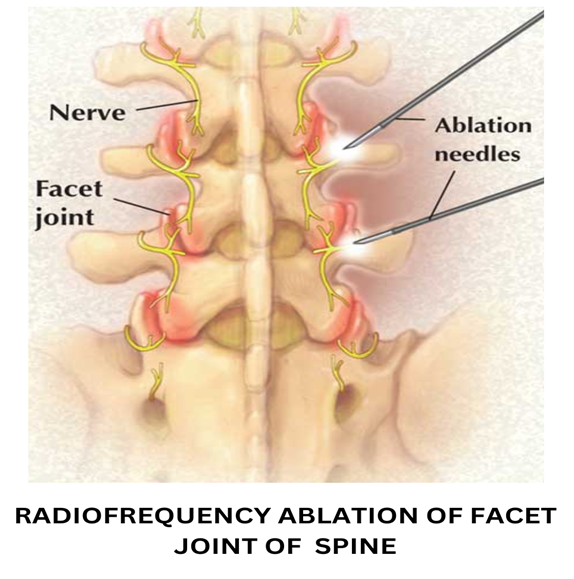

Example 1: One of the causes of backpain is inflammation of facet joints. Nerve supplying the facet joint is called medial branches of dorsal rami of spinal nerves or simply the medial branch. So facet joint is the pain generator and the medial branch is the nerve carrying pain. We can bring relief to this pain by either targeting the facet joint by injecting steroid that brings 3-6 months of pain relief or by targeting the medial branch by a radio frequency which brings 2.5-3 years of pain relief.

4. Medial branch rhizotomy/Radiofrequency ablation(RF):

- Patient selection: Predominant backpain in elderly patients that increases on twisting movements of spine is generally arising from facet joints. These patients have no leg pain.

- Technique: Facet joint pain is carried by medial branches of dorsal rami of spinal nerves or simply the medial branch. This technique damages this nerve, thereby treating the pain. A specialised instrument called radio frequency ablation is used that when set at desired frequency and amplitude produces heat to damage the medial branch.

- Expected result: Results last a minimum of 2.5-3 years after which procedure can be repeated. This technique is therefore better than facet injections.

Example: Facet joint pain is carried by the medial branch. Medial branch rhizotomy/ablation is done using radio frequency and brings a sustained relief in backpain for 2.5-3 years.